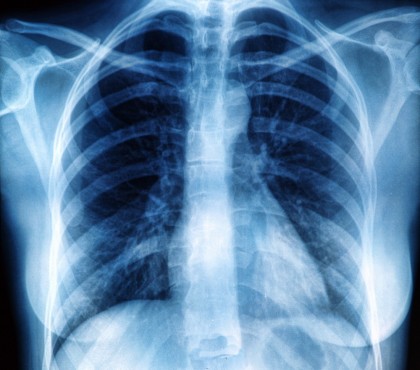

Necesitatea de depistare precoce a cancerului pulmonar în rândul pacienților mai tineri

Conform oamenilor de știință, liniile directoare de screening al cancerului pulmonar în Statele Unite ale Americii sunt reprezentate de pacienții cu vârste de peste 50 de ani, ceea ce determină o ineligibilitate a pacienților tineri pentru screening.

Alexandra Potter, doctor la spitalul american și autor principal al studiului, explică faptul că în cadrul lucrării au fost examinate date aparținând persoanelor cu vârste cuprinse între 20 și 79 de ani din bazele de date United States Cancer Statistics și National Cancer Database care suferă de cancer pulmonar fără celule mici. Eșantionul de studiu a fost compus din aproximativ 40.000 de persoane, observându-se că, din punct de vedere statistic, în intervalul cuprins între anii 2010 și 2018, au fost diagnosticate 1.328 de persoane cu vârsta de 20-29 de ani, 5.682 de persoane cu vârsta de 30-39 de ani și 39.323 de persoane cu vârsta de 40-49 de ani. De asemenea, 75% din pacienții din prima categorie au fost diagnosticați cu cancer pulmonar în stadiul IV, comparativ cu un procent de 40% aferent grupului de vârstă 70-79 de ani.

În plus, specialiștii subliniază faptul că în intervalul de 8 ani analizat, procentul de cancere pulmonare identificate la persoanele cu vârste de până în 50 de ani a rămas constant, însă numărul de persoane de peste 50 de ani diagnosticate cu acesta a crescut semnificativ. Astfel, pe baza acestor date, cercetătorii au ajuns la concluzia că pacienții tineri au un risc mai mare de diagnosticare cu cancer pulmonar în stadiul IV decât persoanele în vârstă, deoarece strategiile de diagnosticare sunt mai dezvoltate pentru cei din a doua categorie. De aceea, autorii sugerează ca depistarea precoce a acestui tip de tumoră să fie realizată pentru fiecare categorie de vârstă, astfel încât și aceștia să beneficieze de reducerea ratei de diagnosticare în stadiile avansate ale bolii, asemenea pacienților de peste 50 de ani. Autorii concluzionează evidențiind și faptul că programele de screening ale persoanelor în vârstă au înregistrat succese semnificative de la introducerea acestora, apreciind că, dacă persoanele tinere ar fi introduse în ele, rata de apariție a formelor terminale de cancer pulmonar ar scădea marcat.